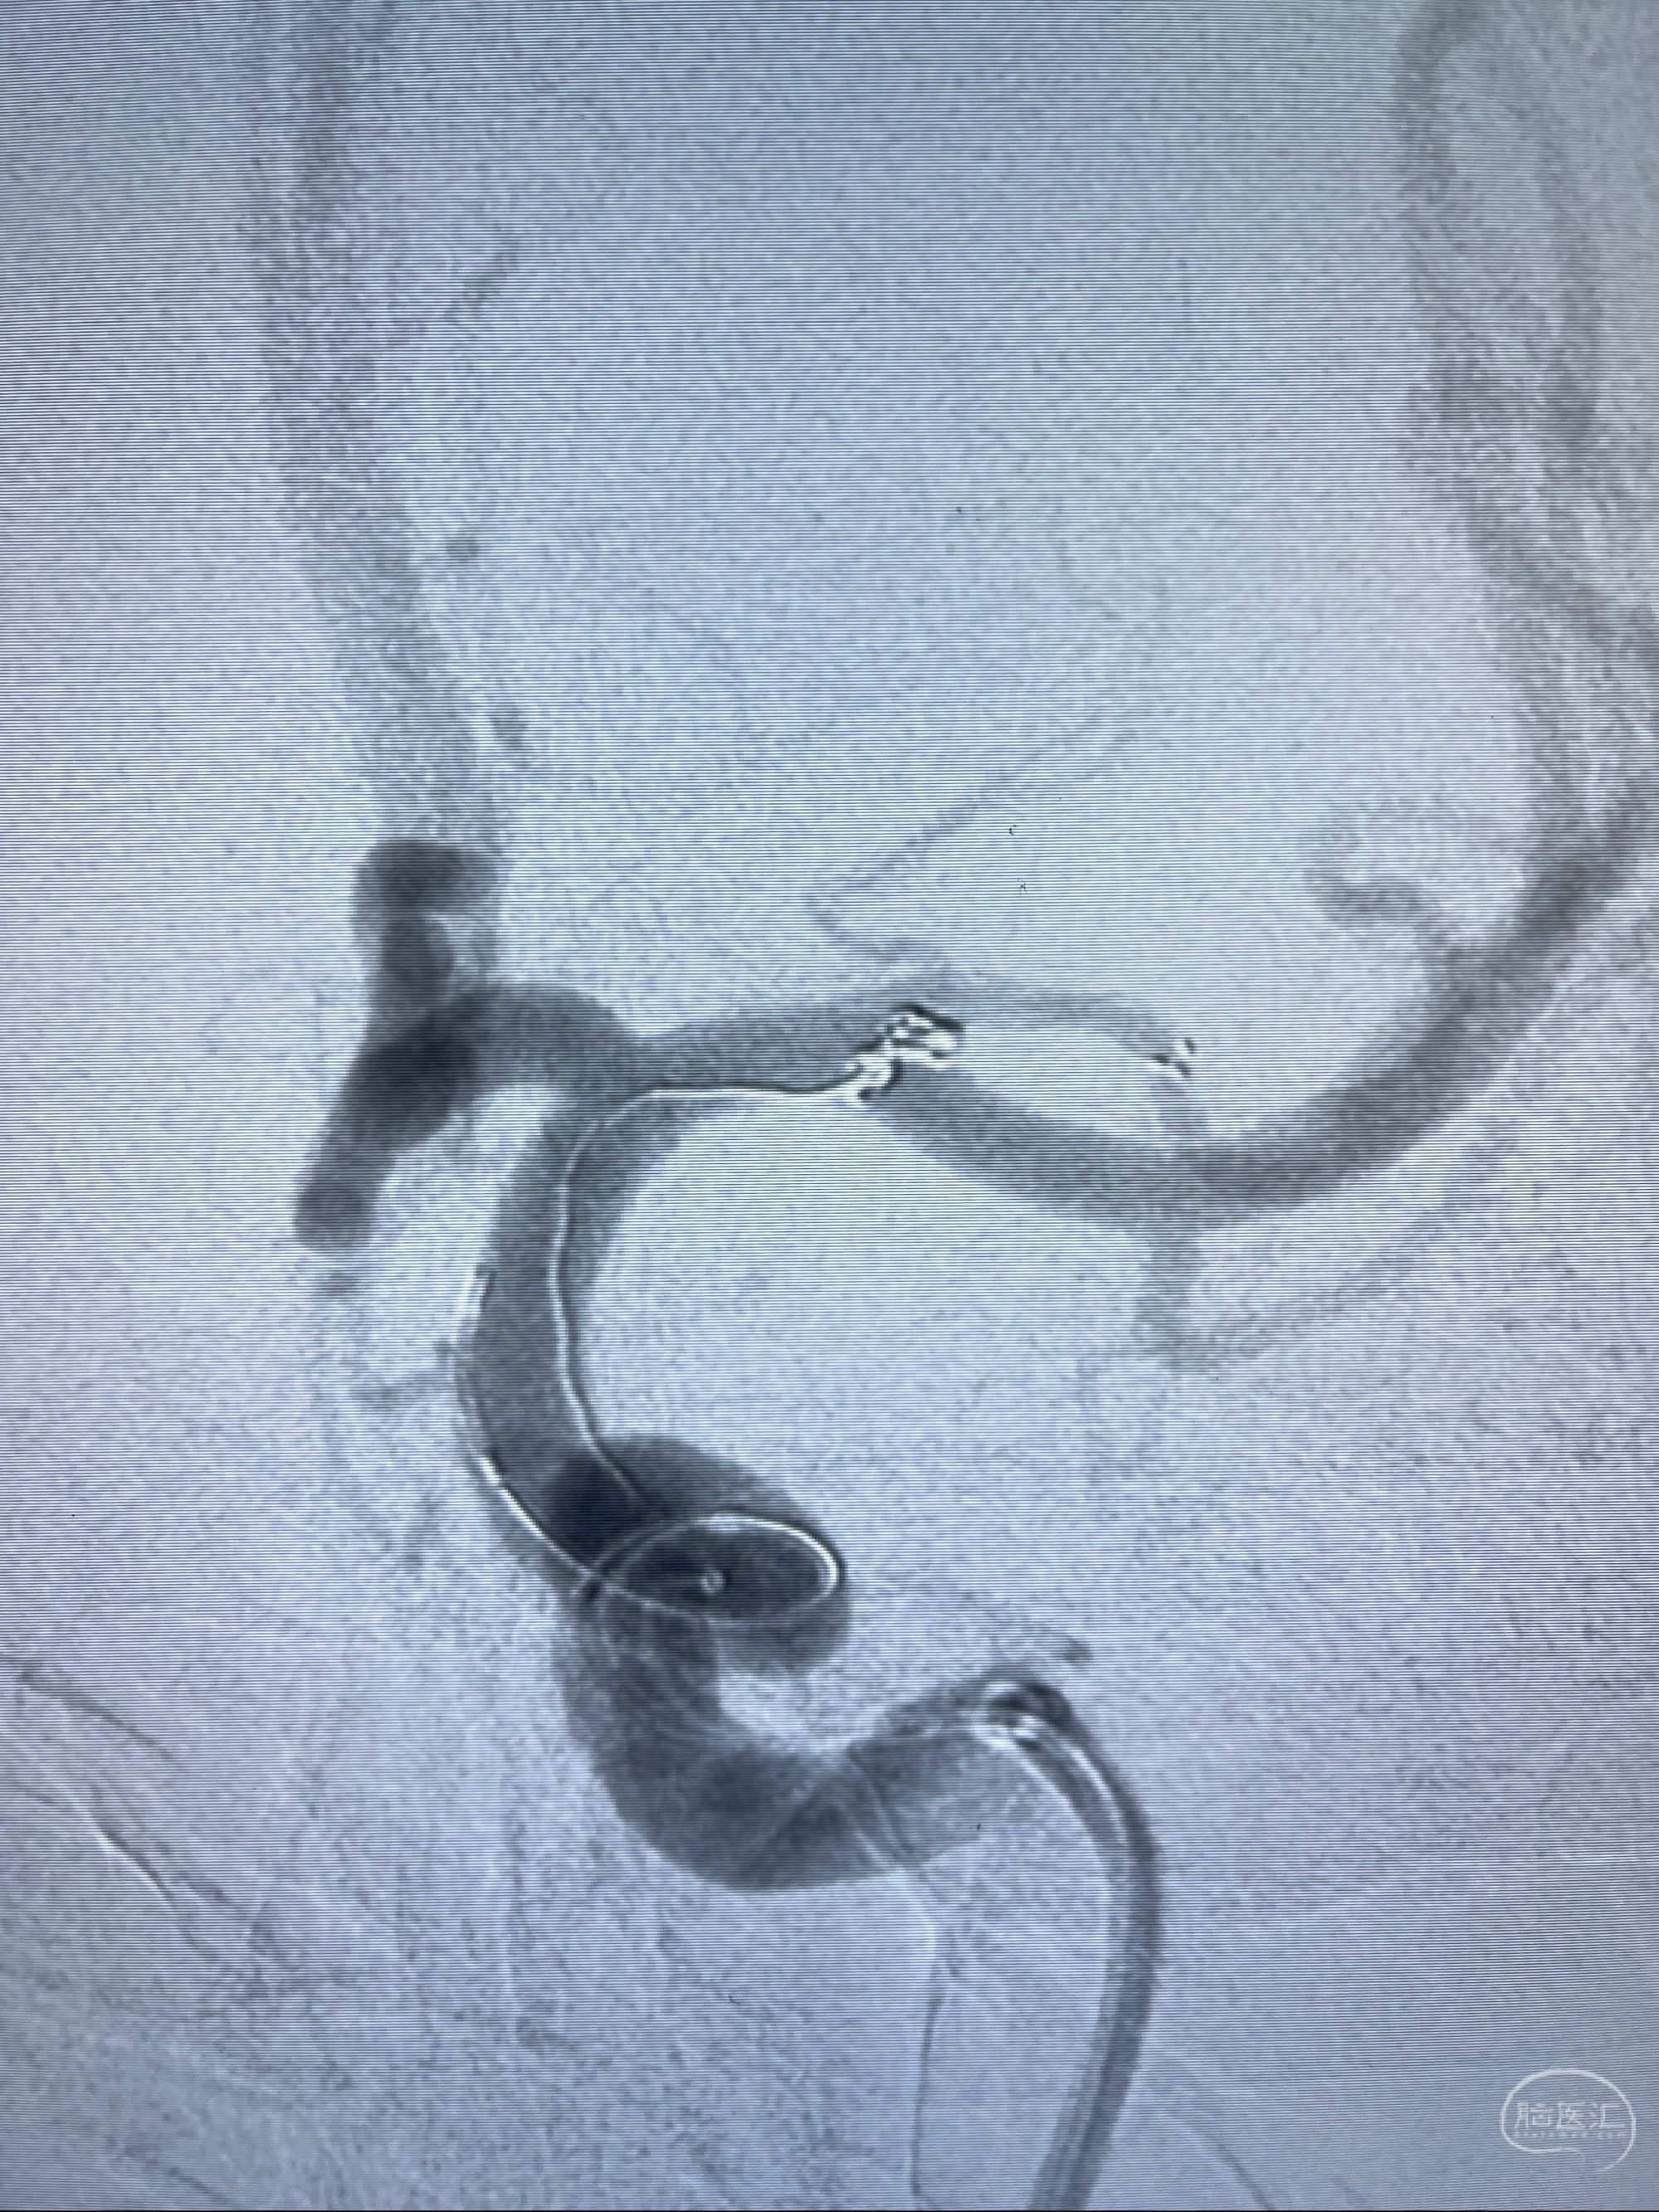

2023-08-14DSA:

左侧大脑中动脉动脉瘤,约2.6-2.8-3.4-2mm大小(瘤颈部、瘤体部、瘤高)